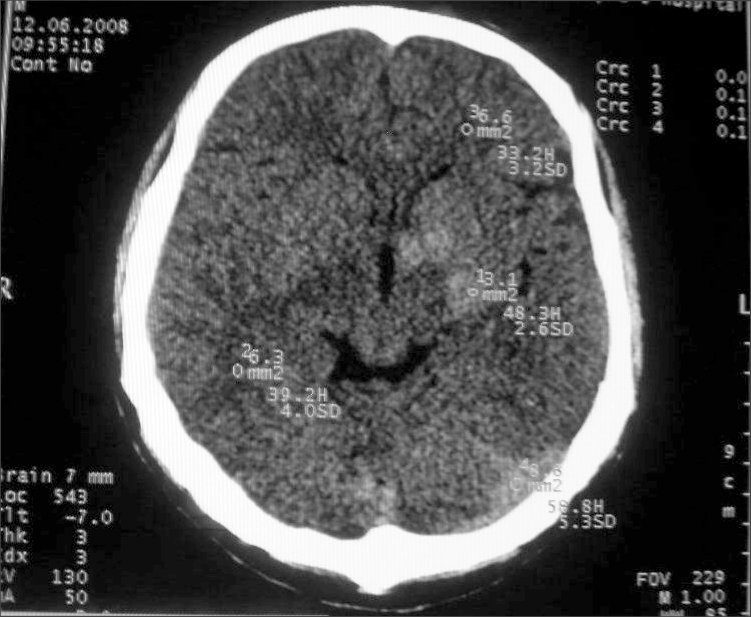

以下是引用守望可可西里在2008-6-13 1:25:00的发言:[br][br] 1.双侧大脑中动脉高密度踌型样接近于全程显示,部分大脑前动脉、基底动脉也呈高密度改变。[br] 2.右侧基底节多发类圆形ct值接近于出血的高密度,边缘模糊。双侧小脑幕及直窦、上矢状窦增宽、模糊。左侧横窦和乙状窦区密度增高、呈云雾状,内缘模糊。[br] 如果这样的表现发生在一个老年人脑部,我们首先会想到是高血压、动脉粥样硬化,就可以很容易得出结论。但这发生在一个20岁年青人的身上,且病程长达半年、临床症状不怎么重,这就比较蹊跷且应该引起高度重视了。[br] 我认为此病人应该是一个血液病患者--双侧大脑中动脉、部分大脑前动脉及基底动脉的高密度改变,只是一个假象:即相对于ct值偏低,只有35的脑灰质而言的相对高密度。而那么多出血改变,则是真正的病变表现。[br] 建议临床进一步进行其他相关的血液、骨髓检查,肝、脾也应该好好检查,应有明显的肿大。